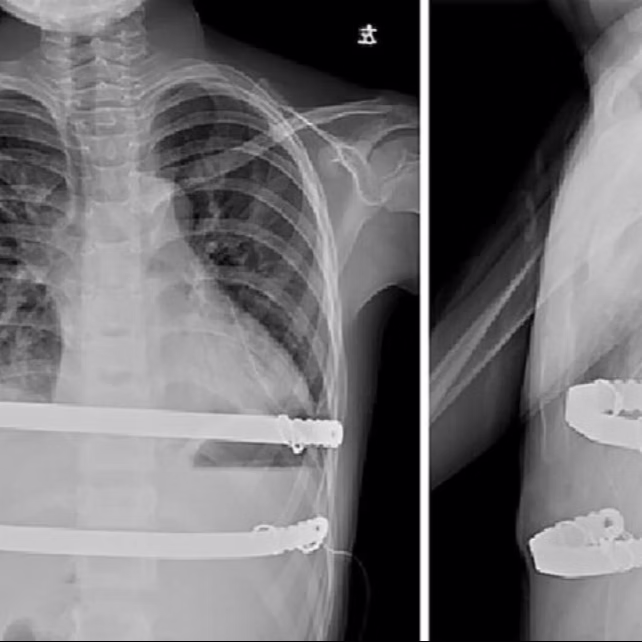

Overview

The Wenlin procedure, pioneered by Dr. Wenlin Wang, is an innovative surgical technique specifically designed for treating pectus carinatum. Compared with the Abramson procedure — the traditional surgical technique for pectus carinatum, the Wenlin procedure shows significant differences in operative details. More importantly, the Wenlin procedure incorporates multiple innovative surgical techniques and concepts, such as the “Wang Technique”, a method for securing the bars, alongside the "Pre-shaping" concept, an approach that involves releasing and shaping the protruding bony structure prior to bar shaping.

Consequently, the Wenlin procedure effectively circumvents the drawbacks and risks of the Abramson procedure. In comparison, the Wenlin procedure offers benefits including smaller trauma, better correction results, safer and simpler operation, shorter postoperative recovery periods, as well as a lower incidence of complications.